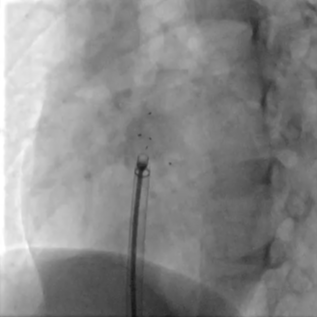

术式入径:采取DSA+经胸超声引导经皮介入的方式。

送入输送系统

沿导丝送入输送鞘

左盘展开

DSA下牵拉成型线使左盘成型,超声可见左盘后撤贴靠房间隔

右盘展开

随后固定钢缆不动,回退鞘管,右盘展开

成型锁定

封堵器双盘扣合住间隔,鞘管抵住封堵器,前顶钢缆。助手固定钢缆和鞘管,牵拉成型线锁定

DSA可见Mark点聚集到一起,多普勒显示即刻阻流效果良好

DSA下可见封堵器整体移动,右盘面未被拉开

DSA下可见Mark点聚拢